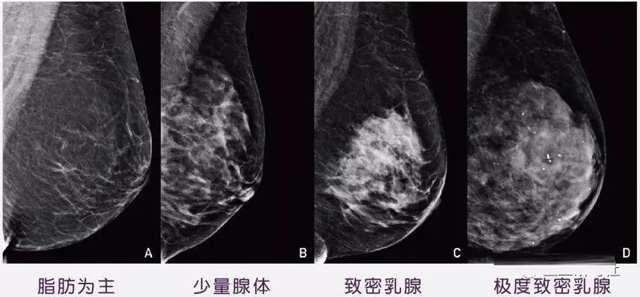

女性乳腺的自我檢查,特別是注意有小結節(jié),腫塊,乳頭有液體滲出情況,需要通過乳腺DR,X光線,磁共振等影像技術檢查。胸的大小跟乳腺癌沒多大關系,乳腺的密度大發(fā)病率高一些,胸小脂肪少致密性大。更容易乳腺癌。這個還不能通過自我檢查來確認。致密乳腺組織看上去是白色或淺灰色需要通過乳腺X射線檢查。